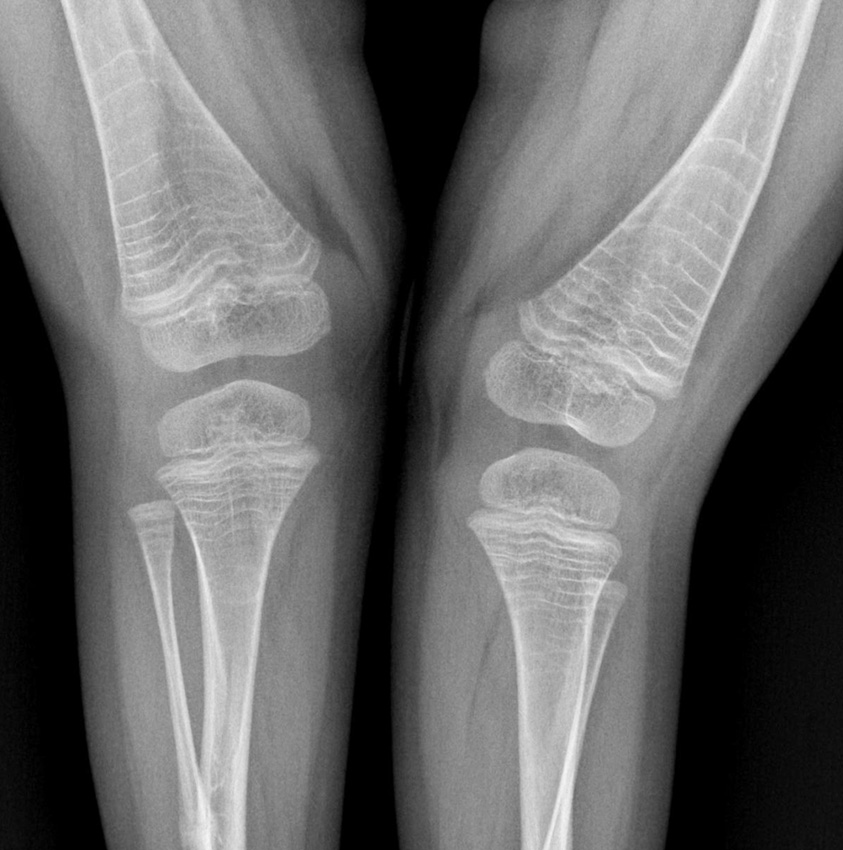

As a result of BP action, the bone remodeling process slows down, leading to increased bone mineralization. The radiographs of long bones show a horizontal line of sclerosis above the growth zone. The number of lines corresponds to the number of BP regimens (Fig. 2). The risk of fracture increases in this zone.

Fig. 2. Lines of bone sclerosis after treatment with bisphosphonates